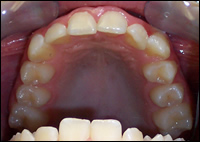

Fig 1 & 2: An 11 year old female presented with a narrow upper and lower dental arches and crowded teeth.